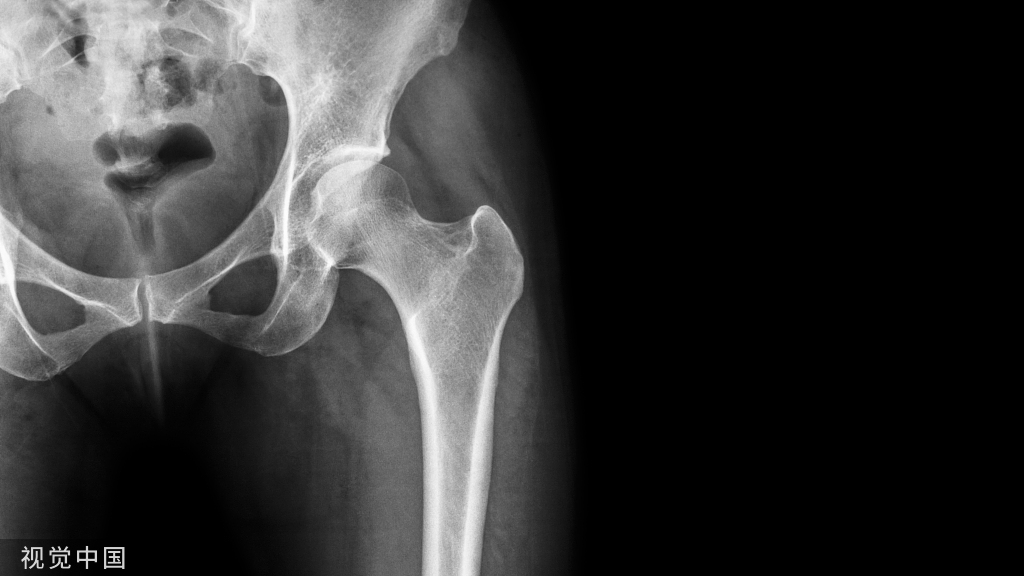

2.4 腰痛、伴根性症状(无危险因素)

常需要开展影像学检查,主要目的是明确根性症状的原因。

腰椎间盘突出是主要原因(A,C),常需要影像学检查。

首选腰椎MRI平扫(A),判断椎间盘突出的敏感度为75%,特异度为 77%,阳性预测值为84%,阴性预测值为64%(A)。此类患者 69%可发现神经根受压征象(C),横断位T2WI 序列是判断神经根受压的关键,准确度为81.8%(B)。

必要时可使用腰椎MRI平扫+增强扫描检查,有助于鉴别椎管内致压物的来源(D)。

腰椎CT平扫临床常用,判断椎间盘突出的敏感度、特异度分别为77.4%、73.7%(A),判断神经根受压的敏感度、特异度及准确度与MRI的一致性较好(B),可协助评估骨质改变及致压物有/无钙(骨)化及严重程度。

腰椎X线平片无法直接显示椎间盘情况。

椎间盘CT造影为有创检查,不适用于初诊患者,且目前临床应用较少。

腰痛、伴根性症状(无危险因素)的检查方法建议见表7。